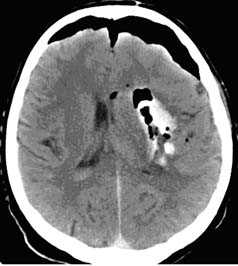

а - Типичные ушибы мозга лобной и височной локализации (стрелки).

б - Геморрагический ушиб правой височной доли (двойная стрелка) с выраженным перифокальным отеком (одинарные стрелки). A-В «Растущие» бифронтальные ушибы у 47-летнего алкоголика. Даты проведения исследований указаны на изображениях. а - Компьютерная томография при диффузном аксональном повреждении.

Многочисленные геморрагические очаги (стрелки), расположенные вдоль средней линии, а также правосторонняя лобновисочная эпидуральная гематома.